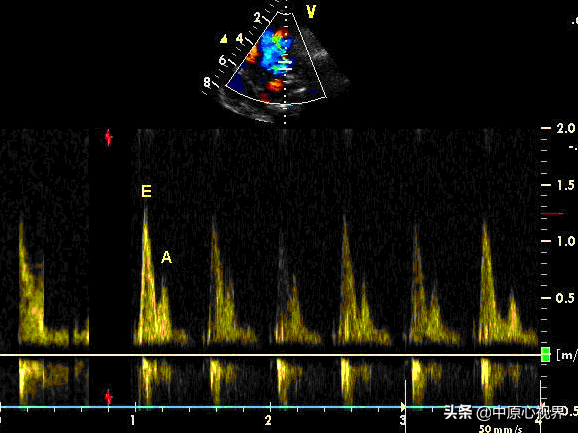

这两个峰是测量心脏舒张期二尖瓣口的前向血流速度的两个峰值。翻译成人话就是:左心室在舒张期从左心房流入的血流不是连续的,而是一股一股的(有些人联想是非常丰富滴)。对,就是一股一股的。正常人的、年轻人的心脏前面的那一股是比后面的那一股要大的,慢慢的,随着年龄的增加,心功能的下降,这两股就会此消彼长。变得逐渐相等,年龄进一步增加,包括一些有害因素的侵袭比如冠心病、酒精性心肌病、扩心病、肥厚性心肌病等等。前面的那一股进一步减少,后面的那一股进一步增大。前面的那一股的大小就可以用血流速度来代替,这就是E峰的来源。后面的那一股就是A峰了。

让我们回到心脏的基础知识上来(你看心脏的基础知识和背景多么的重要)。我们以前认为心脏的收缩是个主动的过程,舒张是个被动的过程。也就是说心脏尤其是左心室收缩完就没事儿了,在那儿干等着,让左心房把血液送入左心室后,左心室扩张,然后再完成下一次收缩,把血液再次泵入主动脉,认为左心室舒张是个被动的过程。现在的研究发现完全不是这么回事儿。左心室在完成收缩后,它会主动舒张,也就是说,这个舒张也是个主动的过程。这个“主动”就会对左心室上游的血液形成一个抽吸作用。越是年轻、功能良好的心脏,它越“主动”,对上游的血液抽吸作用越是明显。这个抽吸作用就会在左心室舒张期形成一个血流峰值,这个峰值就是——E峰。因为左心室的强烈抽吸作用,大部分血液都被抽吸进入左心室了,等到左心房收缩的时候,只残留少部分血液在左心房。这时候左心房再把残余部分血液泵入左心室,起到“补刀”的作用,这个“补刀”就是A峰的来源。在心功能下降后,心肌的顺应性降低,心肌硬化,变得僵硬,它的主动舒张作用就会明显下降,这种情况下E峰就会变得越来越小。据现在的研究认为随着年龄的增加,心肌细胞的能量代谢障碍,其上的钙泵运转能力降低(注意,还没有到失灵的状态),导致心肌细胞内部在舒张期“钙超载”,听说过这个名词吧?没听说过就去翻书! 这种钙泵运转能力的降低就会导致肌动蛋白和肌凝蛋白解离不良。在这种情况下,左心室没有完成的任务就会交给左心房来完成。这时候,左心房的任务加重,A峰就随之上升。左心房的任务一旦超过它的能力,就会出现罢工现象——房颤发生的机制之一。

这个A峰额E峰是怎么测量的呢?它是用心脏彩超,注意不是B超。这两个“超”是有巨大差别的。心脏彩超上有个功能叫:连续多普勒(CW),还有个是脉冲多普勒。这两个“多普勒”各有特点,不要用错了。打开连续多普勒功能,把测量点放到二尖瓣口,就会看到血流图的两个峰值,就是E峰和A峰了!同时机器会有一种啸叫声。这种啸叫声是机器根据血流速度和是否喘流来转化成的音频,非专业人士一般听不懂。所幸目前心内科大夫听得懂听不懂并不影响成为一个合格的心内科大夫。